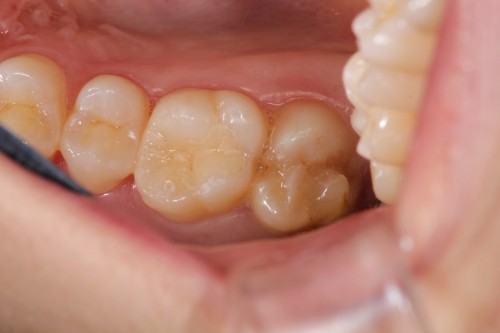

他院で数年前に治療した歯です。白い詰め物がしてありますが、詰め物の奥が虫歯になっております。

白い詰め物と虫歯になった歯のみを取り除きます。通常でしたら型とりを行い、健康な歯まで削って治療する事になります。今回は最小限度しか削ってません。

そしてハイブリッドレジンを詰めました。見た目も噛み心地も問題なく、歯を大きく削る事無く治療を終えました。

ダイレクトボンディング

費用6万円

リスクとして欠ける可能性がある(修復可能)。